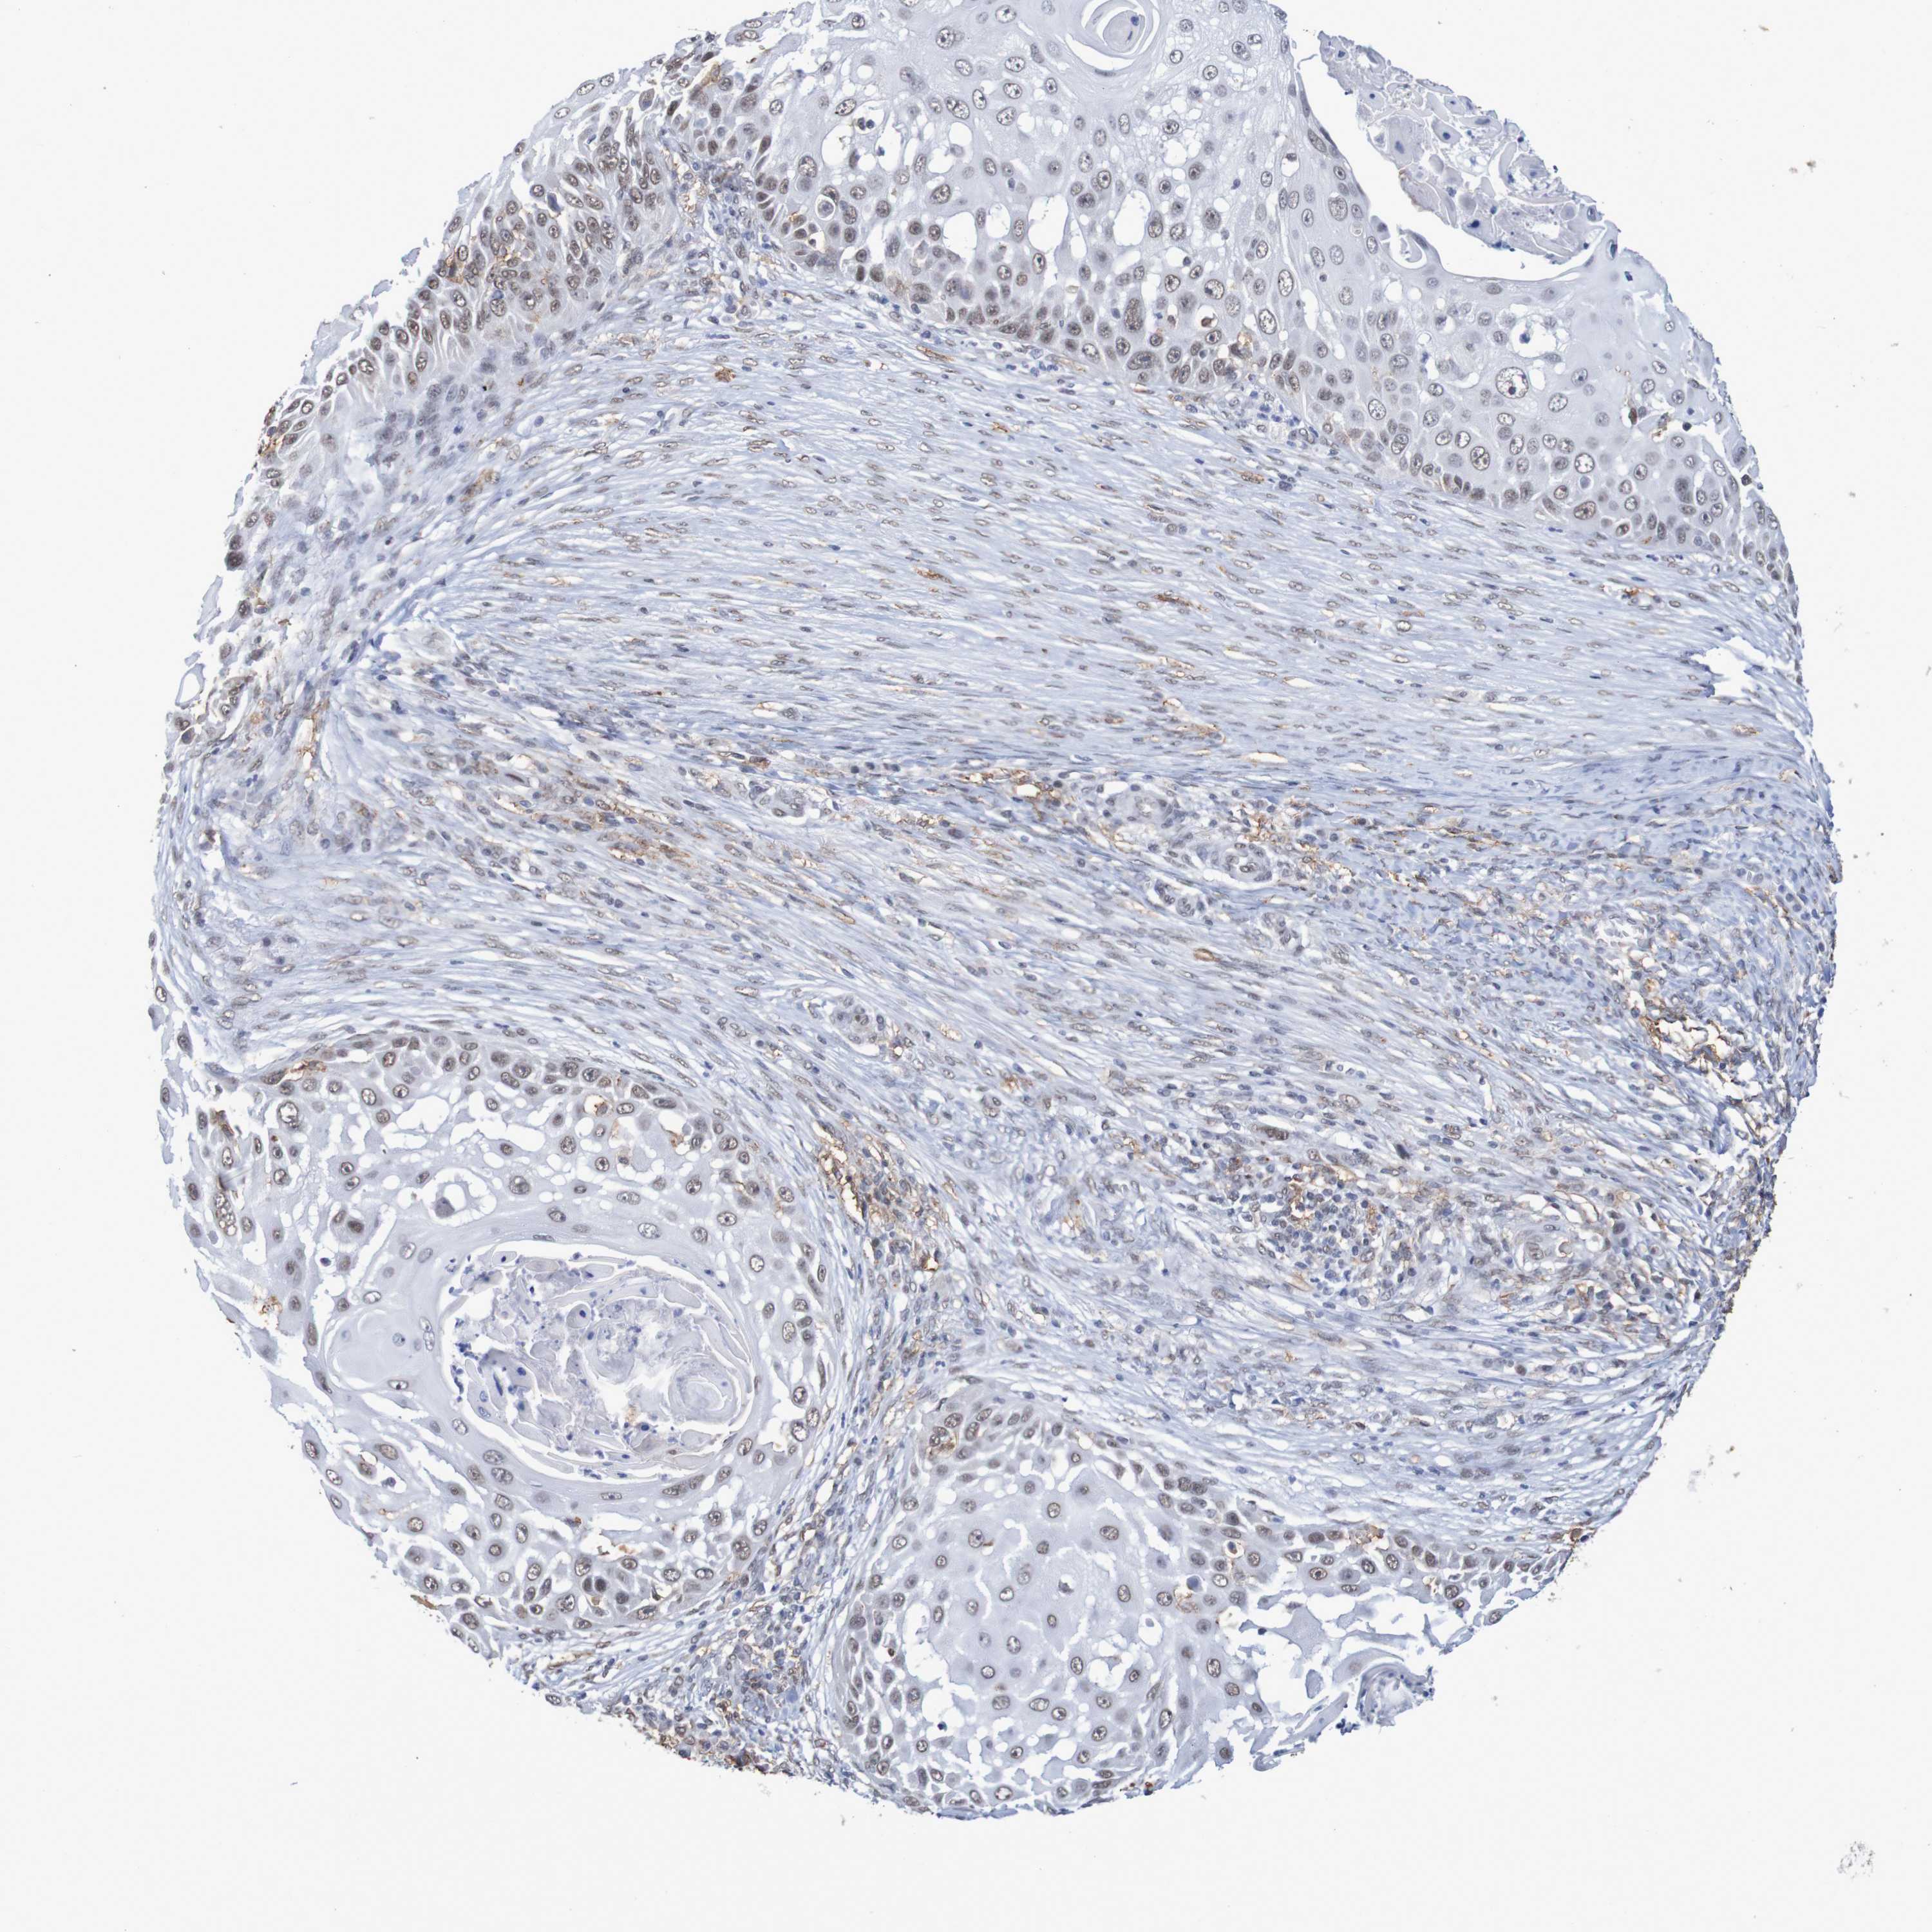

SKIN CANCER - Protein expressioni

A mouse-over function shows sample information and annotation data. Click on an image to view it in a full screen mode. Samples can be filtered based on level of antibody staining by selecting one or several of the following categories: high, medium, low and not detected. The assay and annotation is described here.

Antibody staining in the annotated cell types in the current human tissue is reported as not detected, low, medium, or high, based on conventional immunohistochemistry profiling in selected tissues. This score is based on the combination of the staining intensity and fraction of stained cells.

Each image is clickable and will lead to virtual microscopy that enables deeper exploration of all samples and also displays staining intensity scores, fraction scores and subcellular localization as well as patient and tissue information for each sample.

Antibody HPA011286

Staining

High

Medium

Low

Not detected

Intensity

Strong

Moderate

Weak

Negative

Quantity

>75%

75%-25%

<25%

None

Location

Nuclear

Cytoplasmic/membranous

Cytoplasmic/membranous,nuclear

Squamous cell carcinoma, NOS